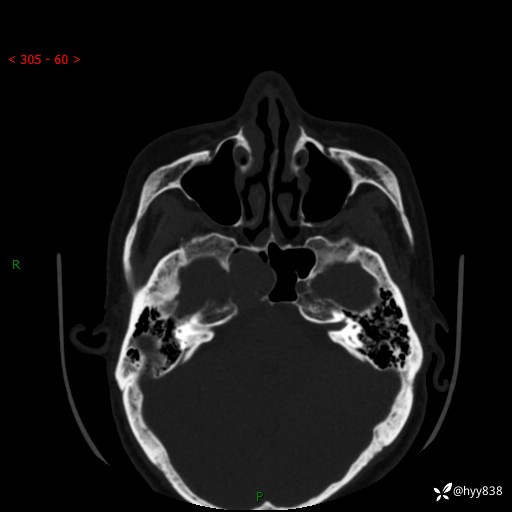

蝶鞍CT平扫